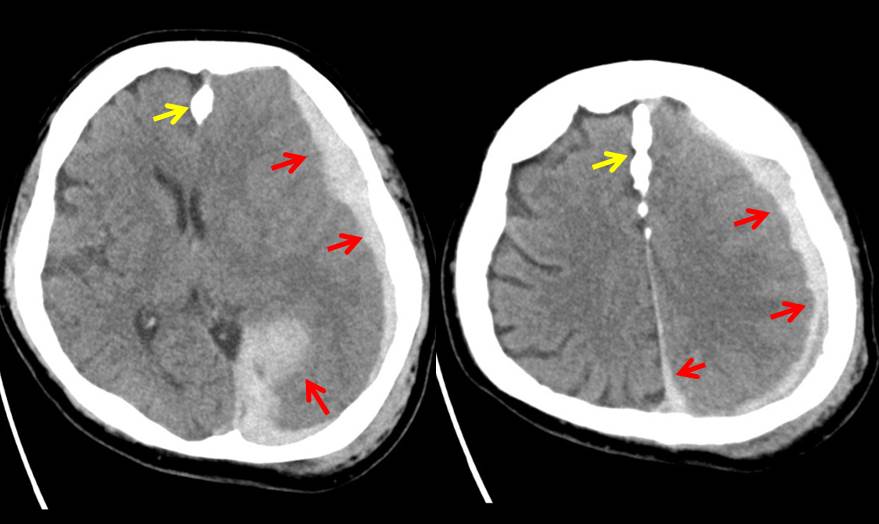

CT Findings

- Acute subdural haemorrhage (red arrows) is seen at left cerebral hemisphere causing compression to the underlying brain parenchyma, particularly at the left temporal -parietal lobe.

- It extends to left interhemispheric fissure and left tentorium

- It has the maximum thickness of 2.0 cm at left tentorium.

- It is associated with effacement of the adjacent sulci and right lateral ventricle. Poor grey white matter junction differentiation of the left cerebral hemisphere in keeping with cerebral oedema

- There is about 1.1 cm midline shift to the left.

- Prominent temporal horn of the left lateral ventricle noted, in keeping with obstructive hydrocephalus.

- No skull fracture.

- Falx calfication (yellow arrows) as noted on skull radiograph

- Scalp hematoma at left parieto-occipital region.